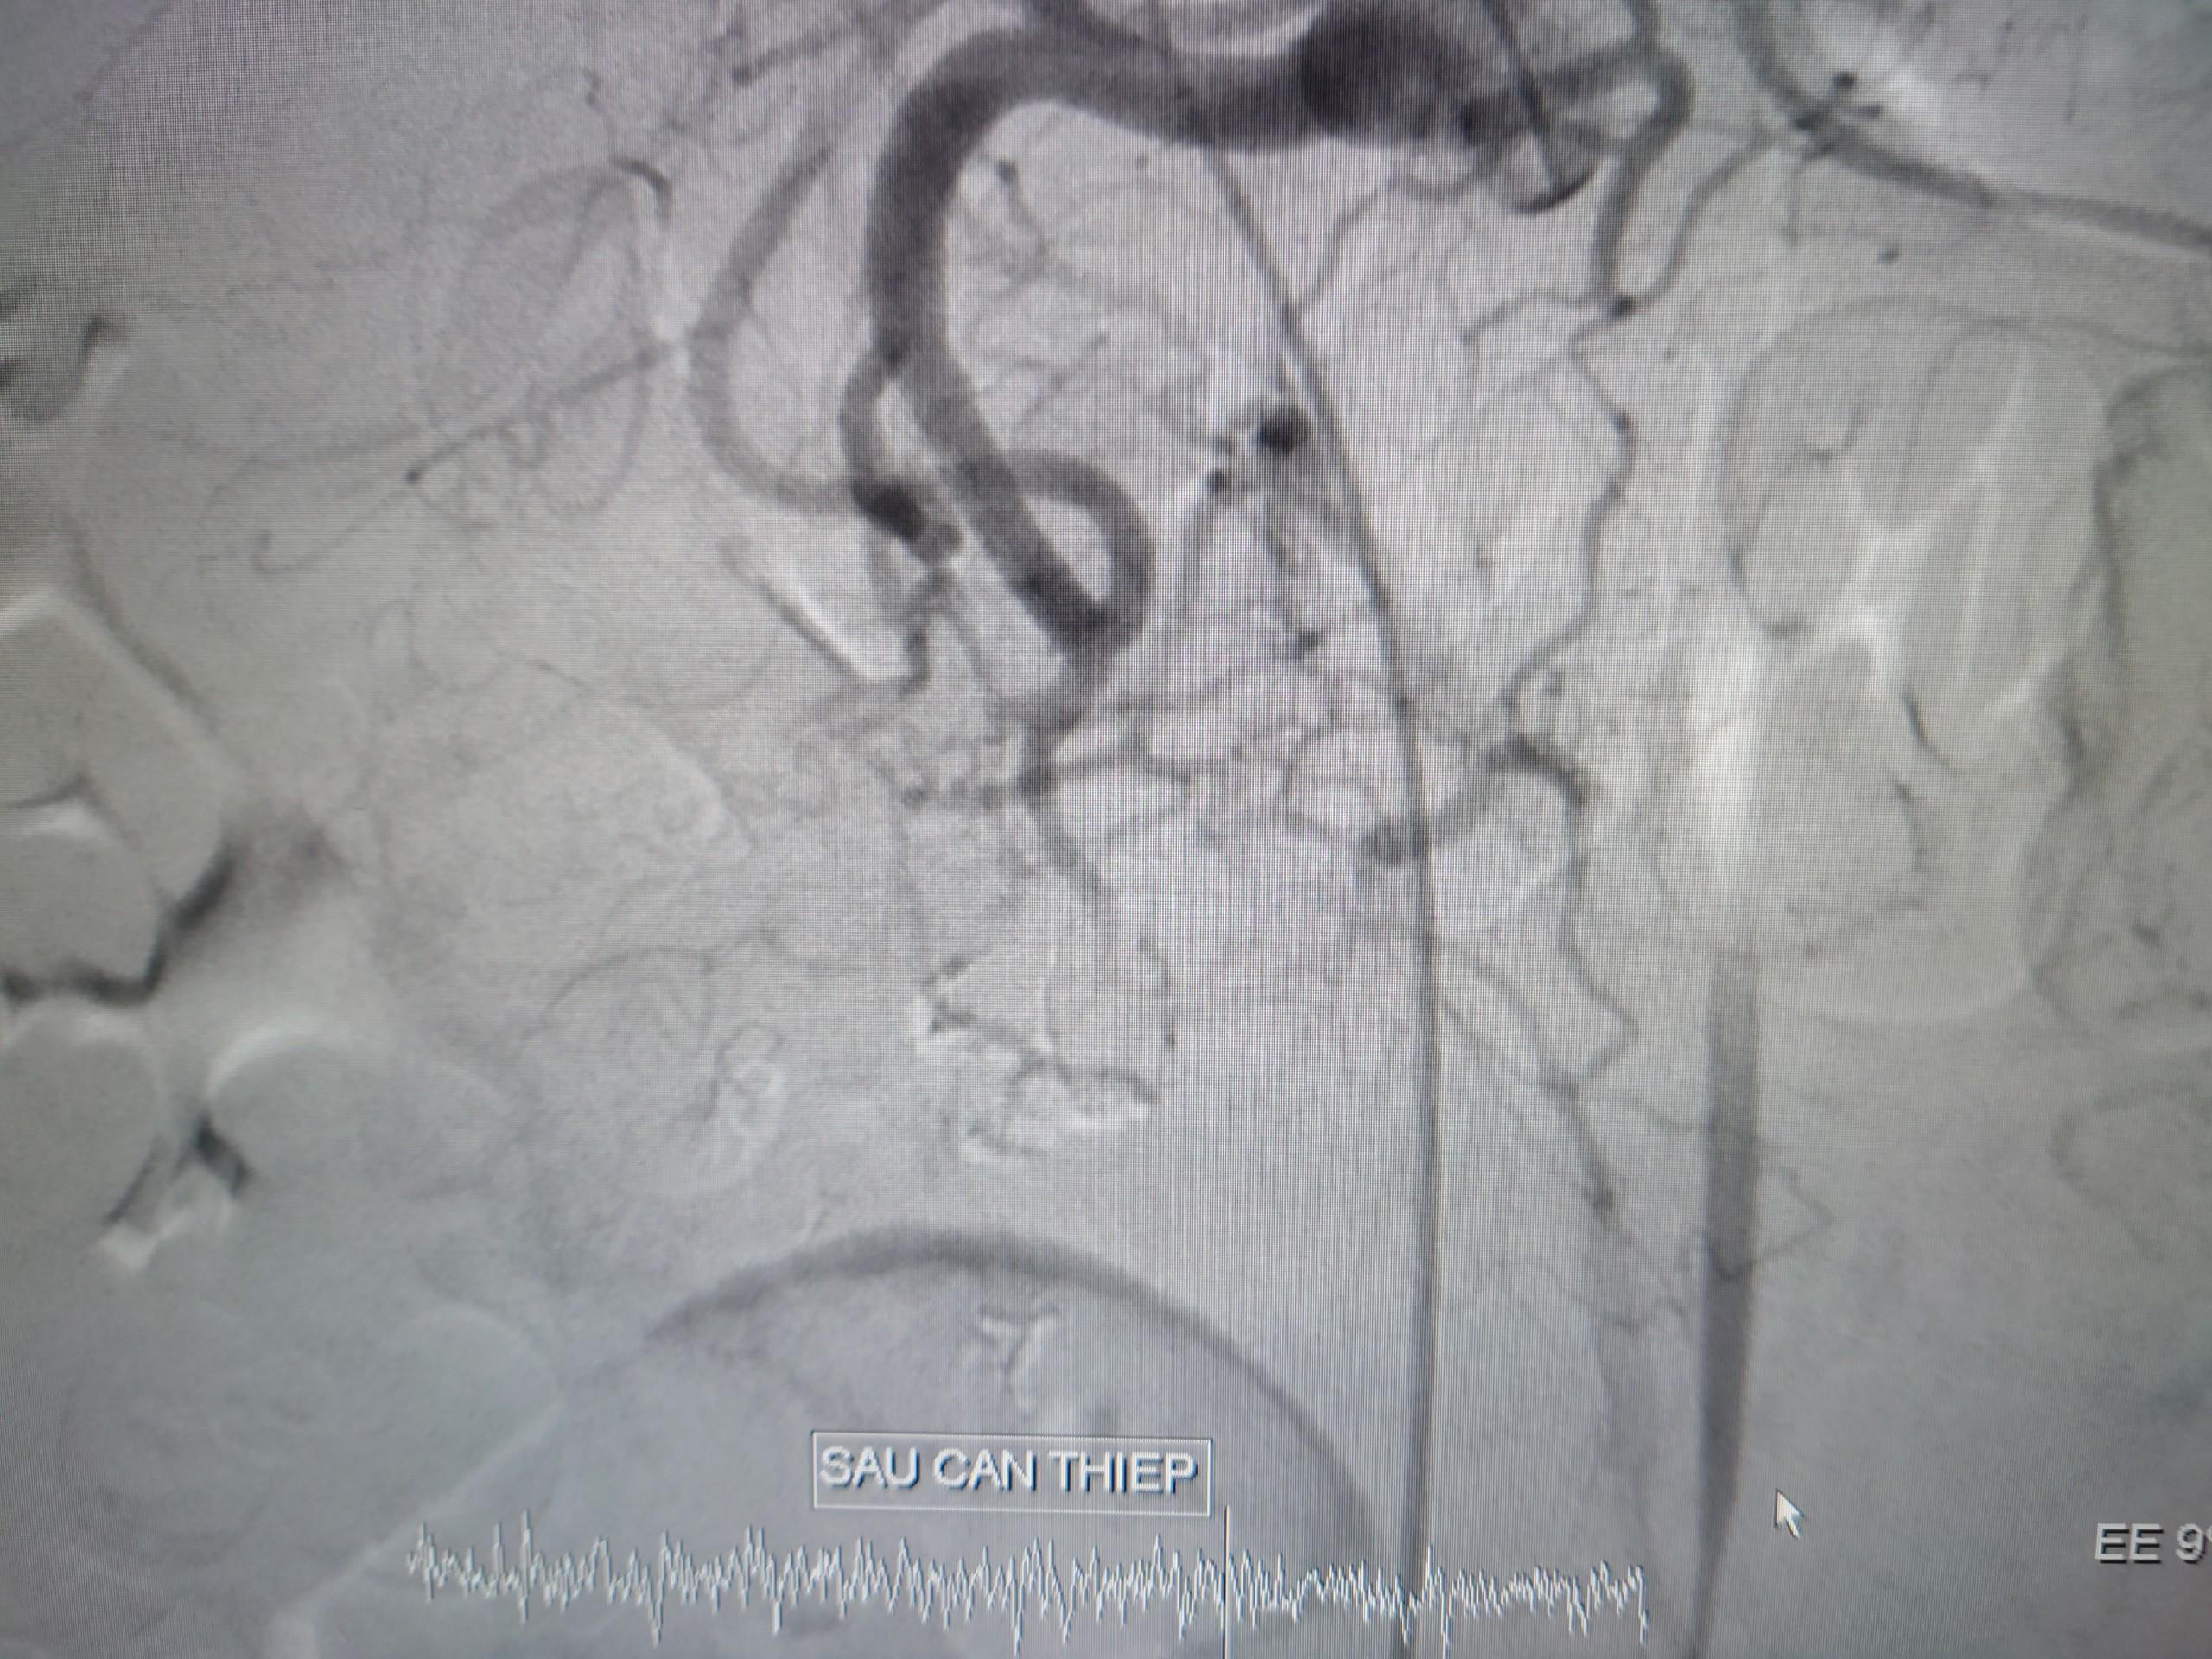

![]() |

Bệnh nhân ổn định sau can thiệp. |